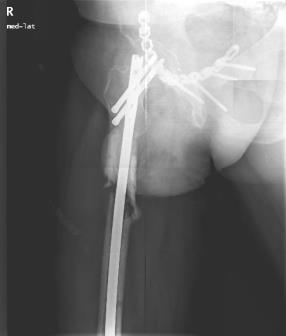

In 14 days, definitive surgery was performed: ORIF for the pelvis and IM-nailing of the femur.

We removed the nail, performed thorough debridement of the IM canal and soft tissues around the surgical wounds and incised and drained the abscess in the mid-thigh through a separate incision. Intraoperative specimens were sent for microbiology assessment. Two microorganisms were grown: Staphylococcus aureus and Enterobacter cloacae. Two weeks later, the fracture was fixed with a nail coated with gentamycin and meropenem loaded cement according to the sensitivity results.